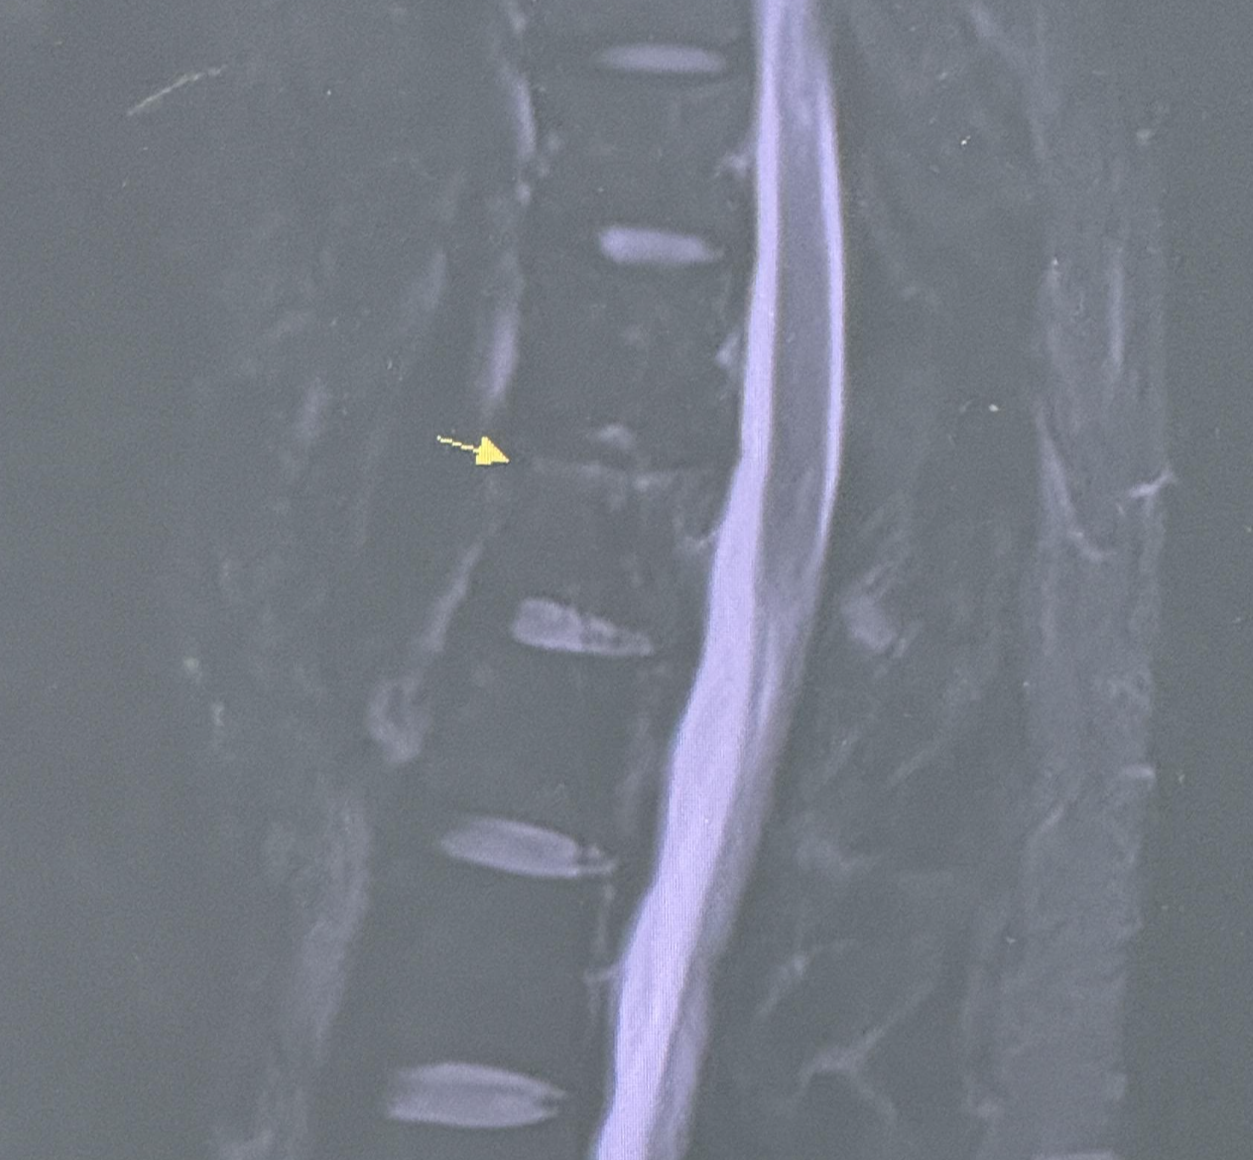

외래로 선생님을 뵙고 그간의 차도를 확인합니다. 어지럽던건 많이 괜찮아졌는데, 수술했던 부위가 아픕니다. 낮에는 약빨로 버티는데 약빨이 떨어지는 자고 일어나는 시점에서는 꽤 많이 아프더군요. 좀 더 지켜보자고 할 것 같았는데 MRI를 찍어보자고 하더랍니다.

MRI를 촬영하고 물리치료까지 진행합니다.

교통사고 치료의 연장선상이라 자동차보험으로 처리된다네요. 제 부담은 없다고 합니다. 그래서 늦은 시간에 MRI를 촬영했고 판독에 시간이 걸리고 외래 진료 시간도 거의 끝나가는지라 MRI 판독 결과는 다음날 보기로 했습니다. 그래서 오늘 9월 5일에 다시 내원하여 MRI 판독 결과를 확인했습니다.

뭐 별거 없겠거니 싶었는데..

수술했던 뼈에 문제가 있다고 하네요.

12번 흉추 위로 골타박상이 좀 있다고 합니다. 일주일은 좀 쉬면서 안정을 취하라는데 그게 가능할리가 있어야죠. 마음같아선 입원을 하며 안정을 취하고 싶습니다만, 추석 전까지 바짝 벌어놓아야 합니다. 그래야 하는데 또 민방위도 껴있고 경기가 별로 없는지라 일도 그리 많지 않네요.

일단 지난 6월에 벗었던 보호대를 다시 착용하고 약 일주일 정도 조심조심 다녀보라 합니다. 약이나 받고 교통사고 치료나 좀 받다 다음 내원일자를 잡을 줄 알았는데 이거 또 일이 꼬여가네요..